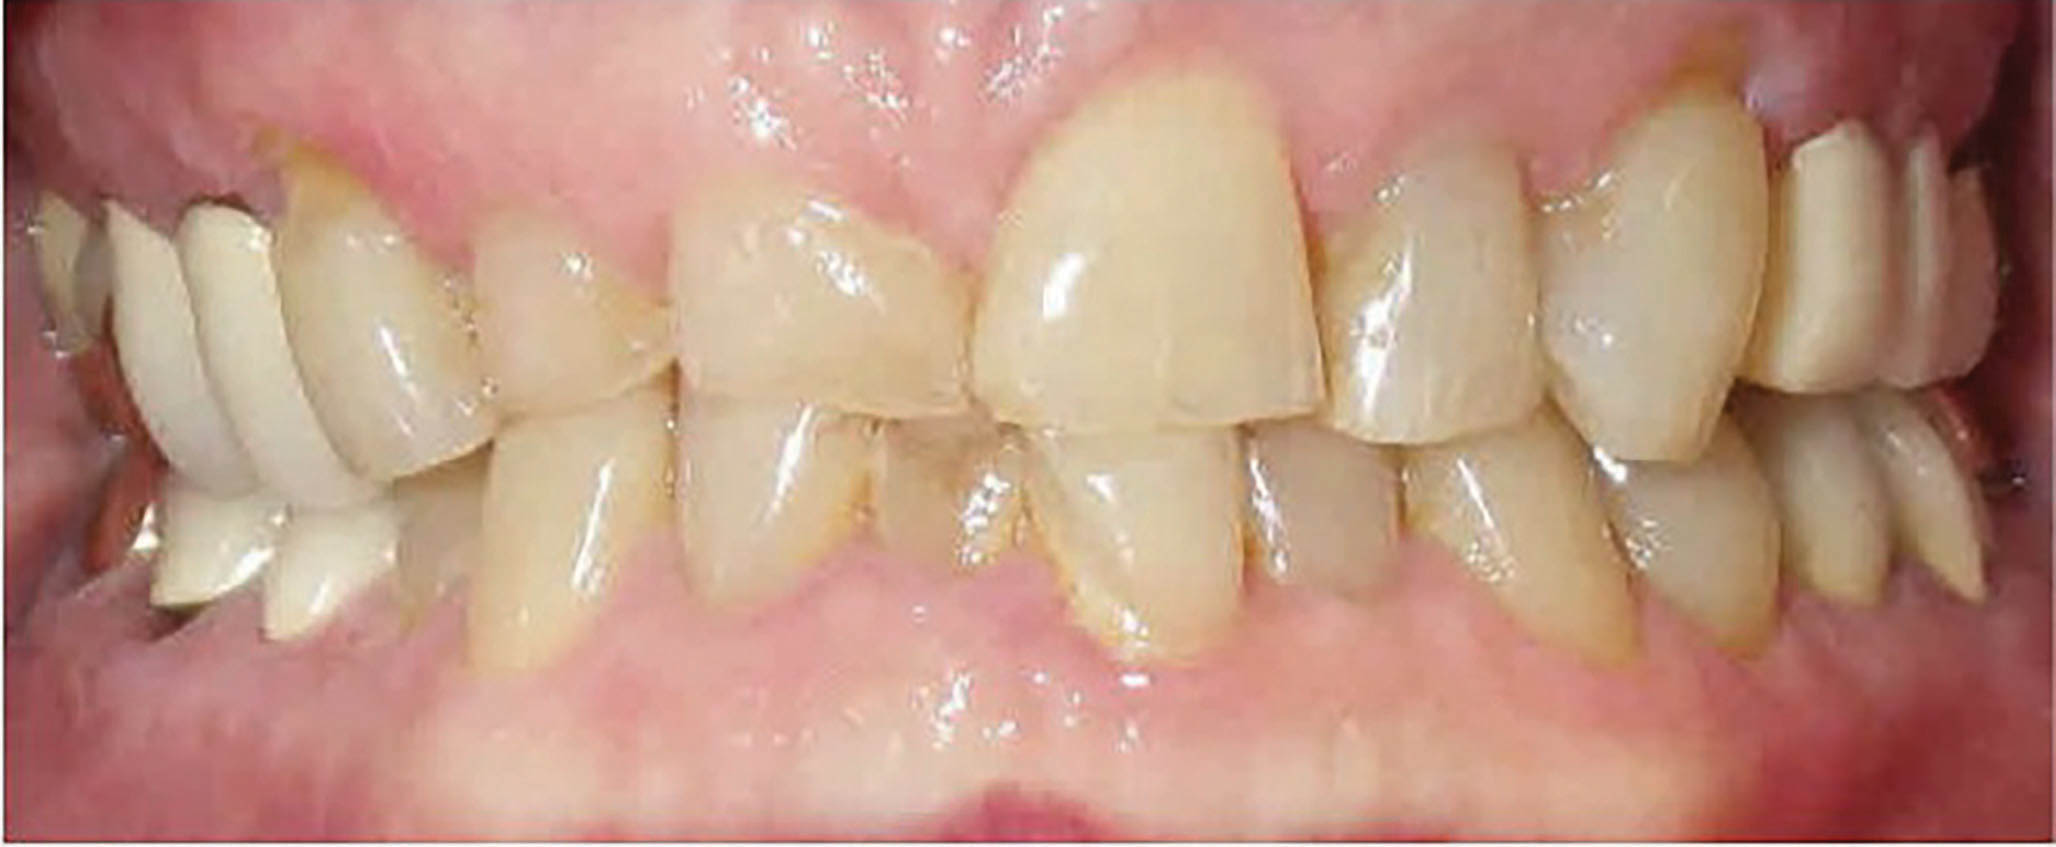

یک خانم ۴۱ ساله با اکلوژن و کرادینگ خفیف در هر دو فک، به همراه اپن بایت را در شکلهای 79-6 الی 81-6 مشاهده مینمایید. اپن بایتهای قدامی با الاینرها به راحتی درمان میشوند. چک لیست او به شرح زیر است:

در این بیمار مولرهای بالا و دندانهای ۴ و ۵ و ۶ پایین را اینترود میکنیم تا به یک کرو اسپی ملایمی هم برسیم. ضمناً کمی هم قدامیهای بالا و پایین را هم اکسترود خواهیم نمود.

شکل 79-6

شکل 80-6

شکل 81-6